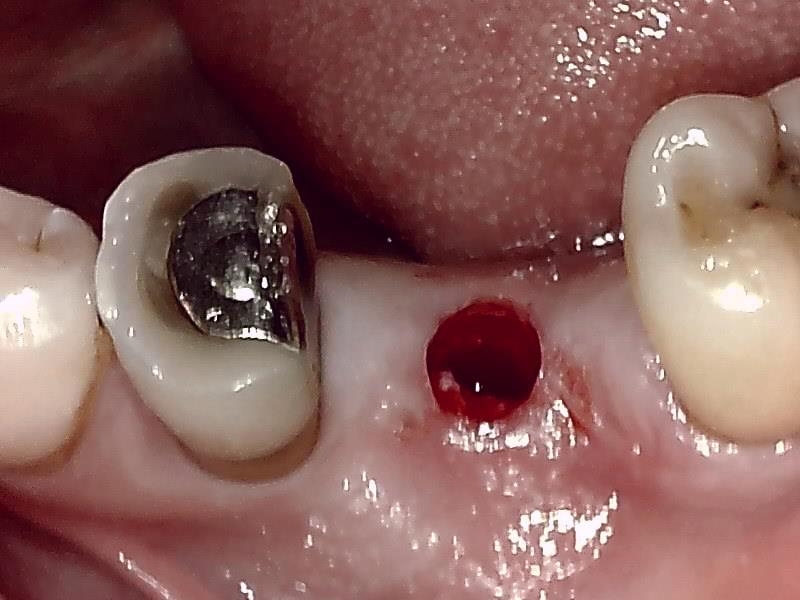

顎堤部 歯槽骨にドリリングする。

インプラント体の口径に合わせて埋入孔を形成した状態です。

術中インプラント埋入した状態は良好です。